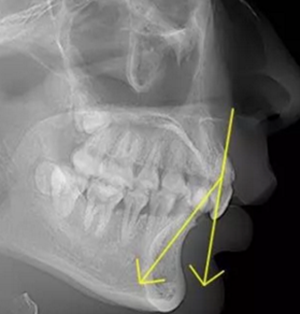

正常情況下,我們的上前牙是蓋在下前牙唇側3mm內(nèi)的,上下切牙牙軸交角為125°左右,

但前牙閉鎖合是上前牙下垂伸長,內(nèi)扣完全鎖住了下切牙,正面觀時我們??床坏较虑醒?,下切牙則常擁擠伸長咬到了上腭內(nèi)的牙齦上,上下前牙發(fā)生的交角幾近180°。

正常前牙交角

前牙閉鎖合交角